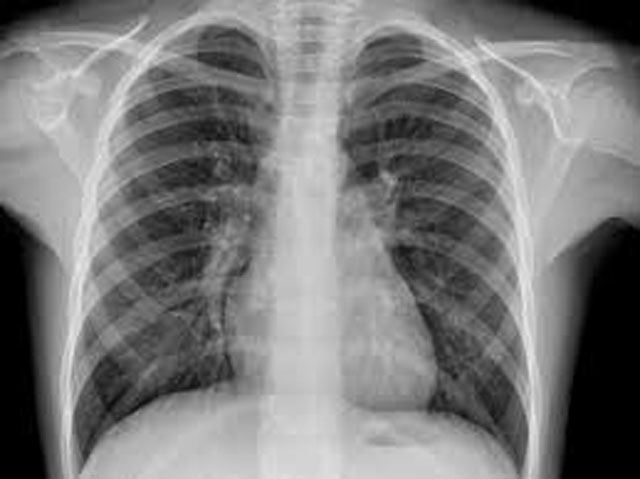

Mumbai, Feb 4: A computer-aided detection (CAD) chest X-ray tool has shown diagnostic accuracy comparable to experienced radiologists in identifying pulmonary tuberculosis (TB) in low-resource, high-burden settings, a retrospective pilot study of nearly 500 patients has found.

The retrospective analysis included chest X-ray films collected between January 1, 2017 and March 30, 2018 in Guinea-Bissau and Ethiopia. Each image was evaluated by CAD software and independently reviewed by two experienced Ethiopian radiologists. To reflect real-world constraints, the study also analysed images captured by photographing X-ray films using mobile phones and a digital camera.

A total of 498 chest X-rays from patients with symptoms suggestive of TB were included. Radiologist A flagged 50 images as TB-indicative, radiologist B identified 99, while the CAD software marked 81.

For Xpert-confirmed pulmonary TB, the CAD tool recorded an area under the receiver operating characteristic curve of 0.84. At a cut-off score of 0.5, the software achieved a sensitivity of 76.5% and specificity of 85.9%. Radiologist A showed sensitivity and specificity of 64.7% and 91.9%, while radiologist B recorded 76.5% and 82.3%, respectively.

Agreement on TB-related findings was described as moderate. The combined agreement between the two radiologists stood at κ=0.45, while agreement between each radiologist and the CAD tool was κ=0.56.

Researchers said the findings suggest CAD chest X-ray tools could play a valuable role in supporting TB diagnosis in settings with limited radiology services, even when images are captured using commonly available devices such as smartphones.